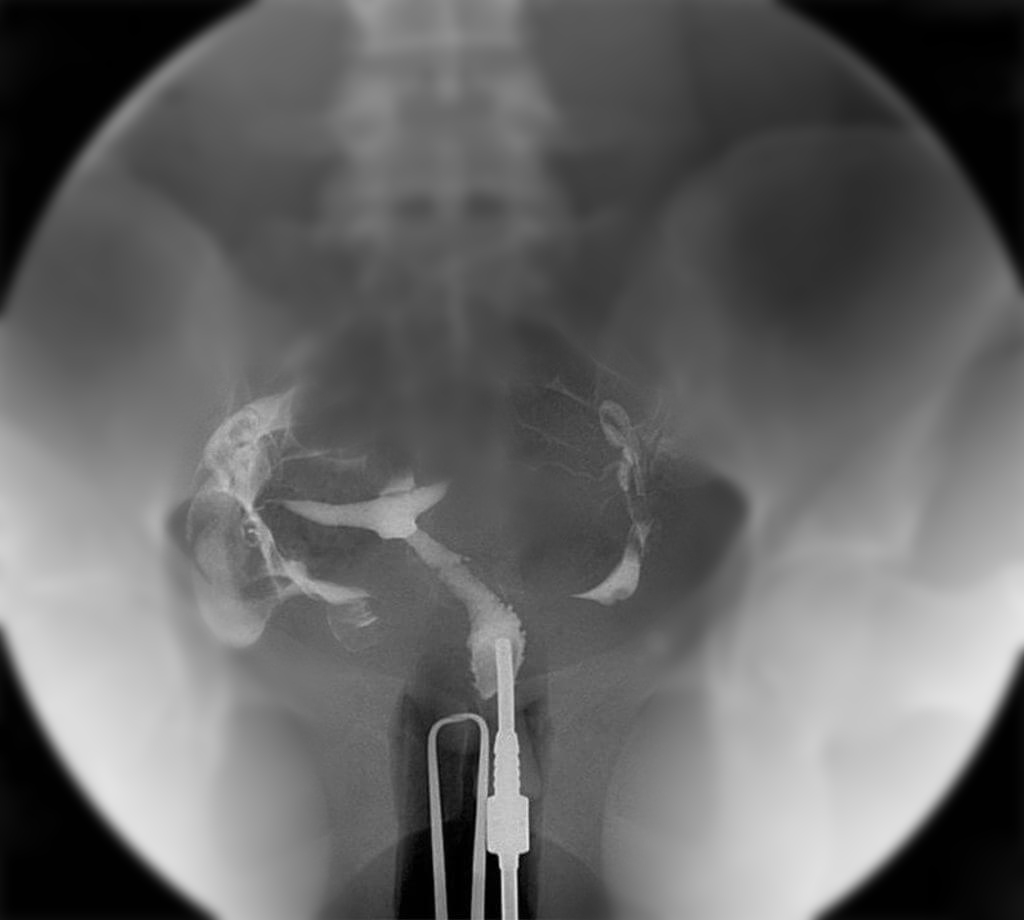

rsds hsg

HSG adalah pemeriksaan radiologi (rontgen) dengan bantuan cairan kontras untuk melihat kondisi rongga rahim dan saluran tuba. Prosedur ini dilakukan untuk mengetahui apakah ada sumbatan, perlengketan, atau kelainan bentuk yang dapat menghambat terjadinya kehamilan.

3. Cairan kontras dimasukkan ke dalam rahim melalui kateter kecil

4. Gambar diambil menggunakan X-ray untuk melihat jalannya cairan